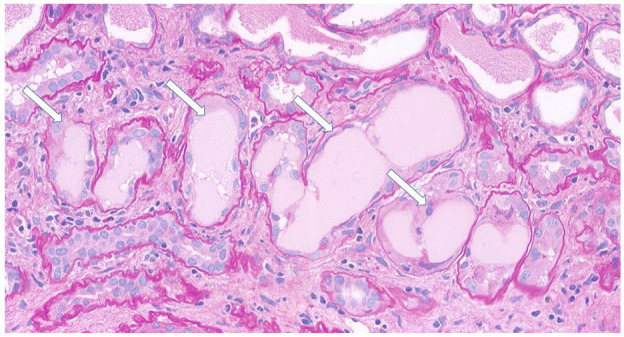

急性肾损伤(AKI)在非霍奇金淋巴瘤有多种病因。我们报告一例由轻链铸型肾病引起的AKI是结外边缘区淋巴瘤的初始表现,没有全身性症状。一名64岁男性,表现为严重AKI,无其他症状。体格检查及肾脏超声检查无明显异常。肾活检显示轻链铸型肾病,随后骨髓活检证实边缘区淋巴瘤。患者接受R-CHOP化疗(利妥昔单抗、环磷酰胺、阿霉素、长春新碱、强的松龙)共6个周期。病人对淋巴瘤有部分反应。然而,他的肾功能没有改善,最终发展为终末期肾病,需要维持血液透析。本病例强调结外边缘区淋巴瘤表现为AKI,强调其在没有全身性症状的情况下独特的肾脏局限性表现,以及肾活检在诊断不明原因AKI中的关键作用。

Acute kidney injury (AKI) in non-Hodgkin lymphoma has diverse etiologies. We report a case in which AKI due to light chain cast nephropathy was the initial manifestation of extranodal marginal zone lymphoma, occurring without systemic symptoms. A 64-year-old male presented with severe AKI without other symptoms. His physical examination and renal ultrasound were unremarkable. Renal biopsy revealed light chain cast nephropathy, and a subsequent bone marrow biopsy confirmed marginal zone lymphoma. The patient received R-CHOP chemotherapy (rituximab, cyclophosphamide, doxorubicin, vincristine, and prednisolone) for a total of six cycles. The patient had a partial response to lymphoma. However, his renal function did not improve, and ultimately he progressed to end-stage kidney disease, requiring maintenance hemodialysis. This case highlights extranodal marginal zone lymphoma presenting as AKI, emphasizing its unique renal-limited manifestation in the absence of systemic symptoms and the critical role of renal biopsy in diagnosing unexplained AKI.